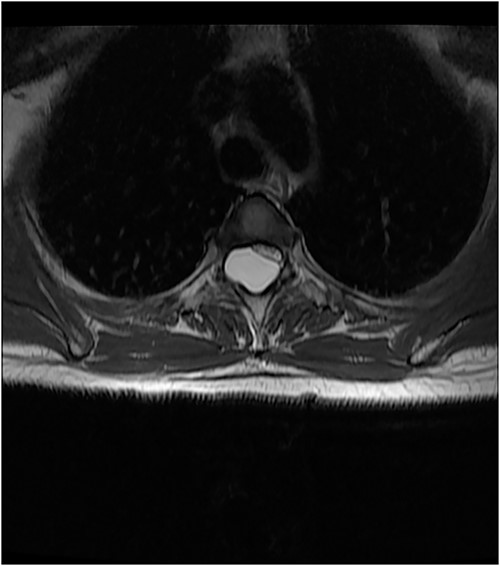

An MRI of the thoracolumbar spine was done, which showed an eccentrically located T4–7 cystic extradural mass causing severe cord compression. The spinal cord was flattened and displaced to the left (Figs 1 and 2).